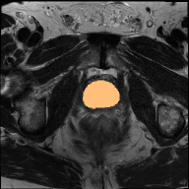

PROMISE12 Dataset: PROMISE12 dataset [18] consists of 50 transverse T2-weighted MRI scans. Following the data split in Liu et al. [19], there are 35, 5, and 10 scans for training, validation, and testing.

Some qualitative segmentation results on the three datasets are shown in Fig. 4, where we can observe that the proposed DSPIF achieves accurate segmentation results.

Results on PROMISE12 Dataset: In Tab. 3, based on MCNet baseline, the proposed method achieves 24.0% Dice and 23.78% JAC (resp., 7.86% Dice and 8.16% JAC) improvement under the setting of using 10% (resp. 20%) labeled data. Compared with state-of-the-art method BCP [3], the proposed method built on CPS [10] achieves an improvement of 3.89% (resp. 3.73%) Dice when using 10% (resp. 20%) labeled data.